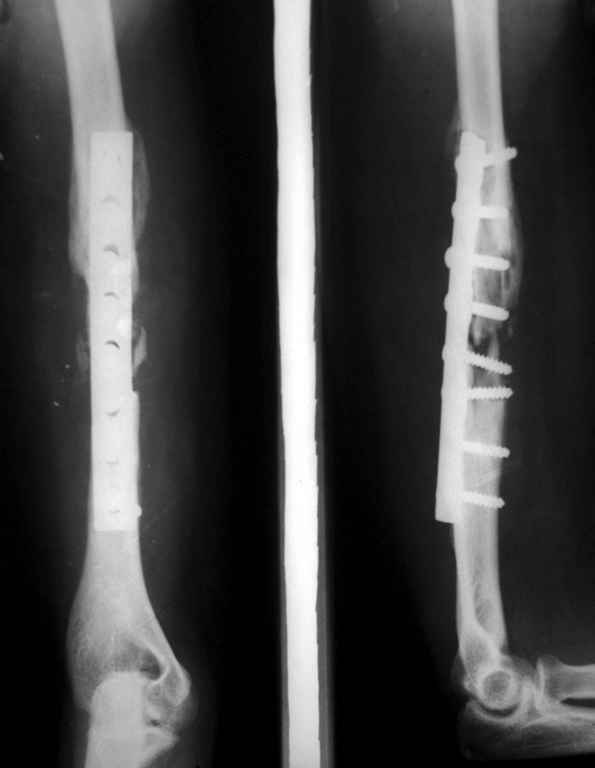

[Ortho] Ложный сустав плечевой кости

Владимир.Выделяем свои малоберцовую кость практически

полность.Выпиливаем замок там и тут. Синтез. Не типичный случай,но

перестраивается хорошо даже диафиз. рЕНТГЕН ПРИЛАГАЮ

Вложение не в текстовом формате было извлечено…

Имя     : Рисунок2.jpg

Тип     : image/jpeg

Размер  : 17800 байтов

Url     : http://weborto.net:8080/pipermail/ortho/attachments/20100208/ce18b105/attachment-0004.jpg